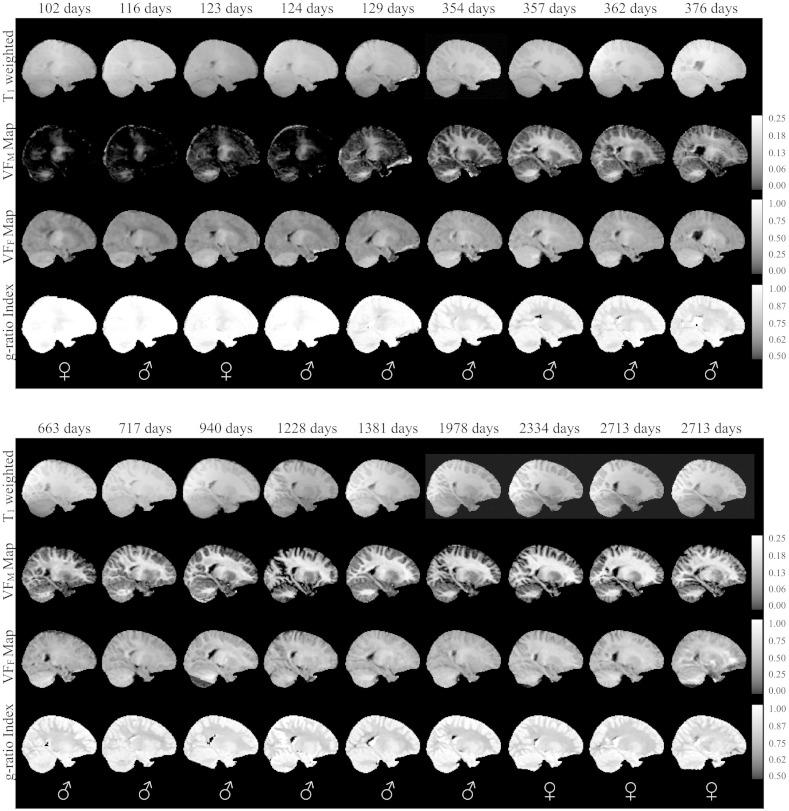

Optimal myelination of neuronal axons is essential for effective brain and cognitive function. The ratio of the axon diameter to the outer fiber diameter, known as the g-ratio, is a reliable measure to assess axonal myelination and is an important index reflecting the efficiency and maximal conduction velocity of white matter pathways. Although advanced neuroimaging techniques including multicomponent relaxometry (MCR) and diffusion tensor imaging afford insight into the microstructural characteristics of brain tissue, by themselves they do not allow direct analysis of the myelin g-ratio. Here, we show that by combining myelin content information (obtained with mcDESPOT MCR) with neurite density information (obtained through NODDI diffusion imaging) an index of the myelin g-ratio may be estimated. Using this framework, we present the first quantitative study of myelin g-ratio index changes across childhood, examining 18 typically developing children 3months to 7.5years of age. We report a spatio-temporal pattern of maturation that is consistent with histological and developmental MRI studies, as well as theoretical studies of the myelin g-ratio. This work represents the first ever in vivo visualization of the evolution of white matter g-ratio indices throughout early childhood.

神经元轴突的最佳髓鞘形成对于有效的大脑和认知功能至关重要。轴突直径与外纤维直径的比值,即g比值,是评估轴突髓鞘形成的可靠指标,也是反映白质通路效率和最大传导速度的重要指标。尽管包括多组分弛豫测量法(MCR)和扩散张量成像在内的先进神经成像技术能够洞察脑组织的微观结构特征,但它们本身无法直接分析髓鞘g比值。在此,我们表明,通过将髓鞘含量信息(通过mcDESPOT MCR获得)与神经突密度信息(通过NODDI扩散成像获得)相结合,可以估算髓鞘g比值指数。利用这一框架,我们首次对儿童期髓鞘g比值指数的变化进行了定量研究,对18名3个月至7.5岁的正常发育儿童进行了检查。我们报告了一种时空成熟模式,这与组织学和发育性MRI研究以及髓鞘g比值的理论研究一致。这项工作代表了首次在体内可视化整个幼儿期白质g比值指数的演变。